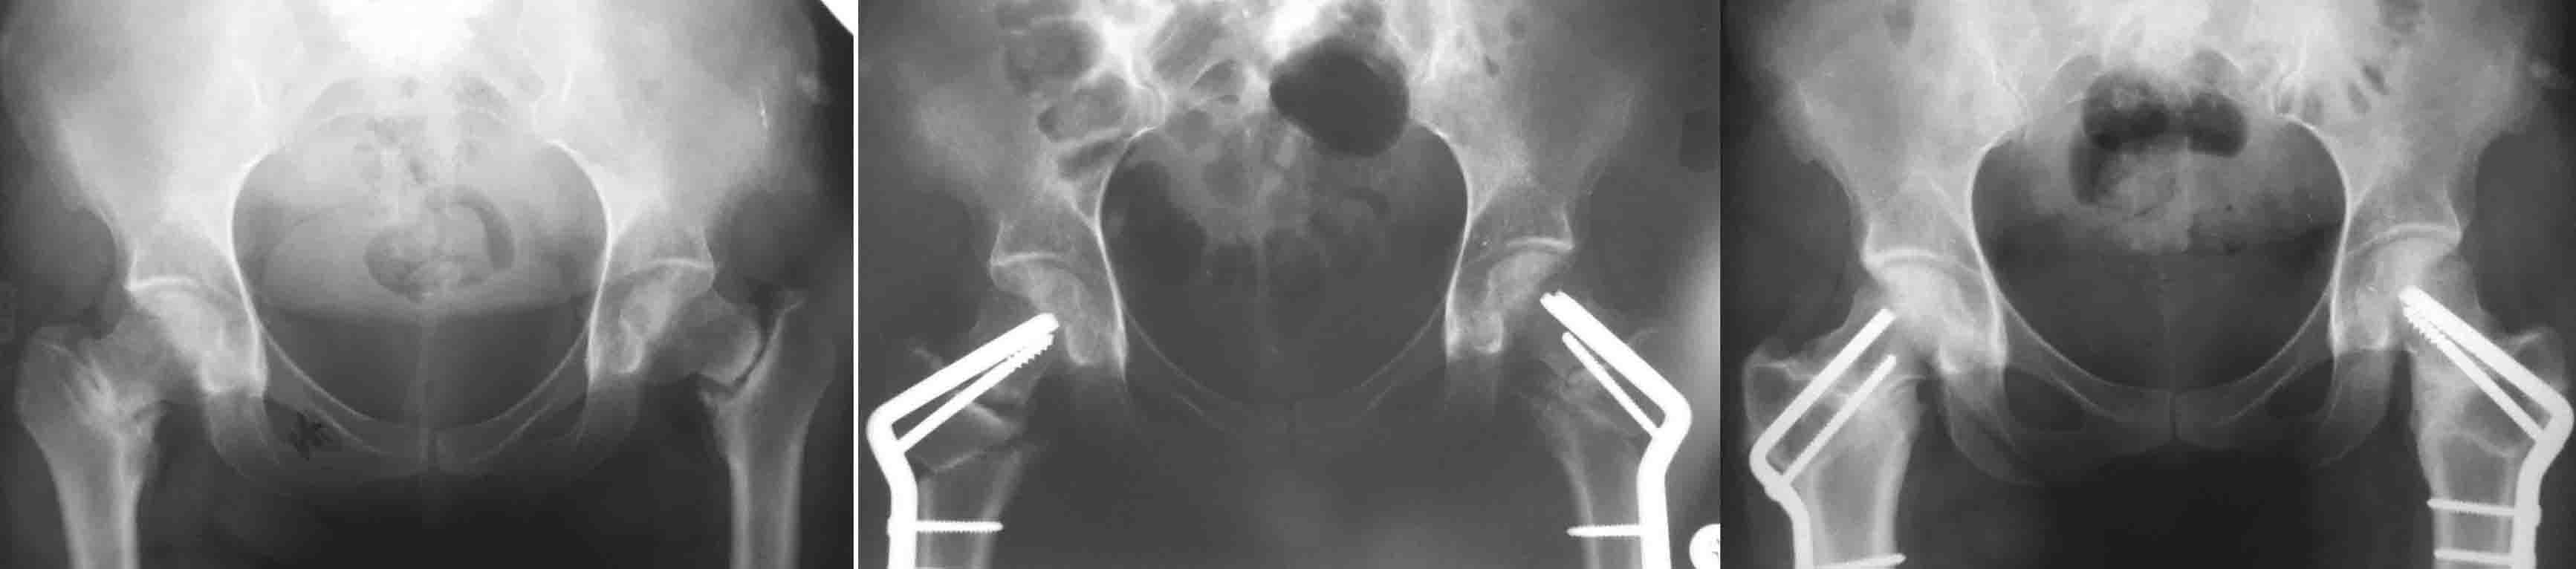

И клинковые и DHS, это всего лишь способ остеосинтеза, хотя, наверное, клинковые дают большую ротационную стабильность (по оси шейки), менее травматичны. Но это не постулат (1943 J Bone Joint Surg Am.;25:319-339. W. P. Blount BLADE-PLATE INTERNAL FIXATION FOR HIGH FEMORAL OSTEOTUMIES). При подвертельных остеотомиях с латерализацией клинковые пластины метод выбора (по другому латерализацию дистального не выполнишь). Оптимальними являються рассчеты СORA по Dror Paley (centr rotation and angulation). Взяты из книги Principles of Deformity Correction by Dror Paley. Для примера межвертельные при двусторонних ложных cуставах шеек.